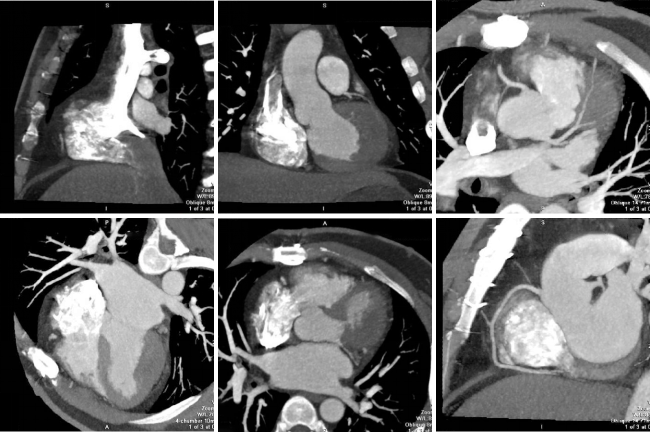

病例二 男,30歲, 右心房占位性病變,心功能Ⅱ級(jí),心律失常,心房纖顫, 平均心室率92次/分。

術(shù)前CT檢查:

右心房增大,其內(nèi)可見(jiàn)占位性病變,通過(guò)獨(dú)有的三維染色后處理,可以對(duì)腫瘤進(jìn)行染色, 以便于確定腫塊與心臟血管及其他周圍結(jié)構(gòu)的關(guān)系。

心臟彩超及食道超聲可見(jiàn)右房?jī)?nèi)囊性占位病變;室間隔及左室壁厚度正常高限;雙房大; 左室收縮功能正常; 彩色血流示: 各瓣膜未見(jiàn)病理性返流。

腫瘤病理結(jié)果與CT檢查顯示的大小、 形態(tài)相符合。

術(shù)后CT檢查:

術(shù)后可見(jiàn)右房形態(tài)正常, 心臟其余各結(jié)構(gòu)未見(jiàn)明顯異常。

640層寬體探測(cè)器CT實(shí)現(xiàn)了3 20排譜黃金寬體探測(cè)器1 6 cm的 超寬覆蓋范圍, 與2 7 ms超 快時(shí) 間 分 辨 率 的 完 美 結(jié) 合 , 可 以 實(shí) 現(xiàn) 微 劑 量 高 清 全 景 電 影 成 像 。 特 別 是 在 冠 脈 檢 查 上 , 可 以 實(shí) 現(xiàn)一次心跳下的心臟冠脈檢查, 實(shí)現(xiàn)復(fù)雜心率情況下高清冠脈成像的100 % 檢查成功率。

此外,強(qiáng)大的后處理功能,能提取心臟冠脈,明確腫瘤大小、形態(tài)、表面特征、位置及三維展示與周圍結(jié)構(gòu)的關(guān)系,還能提供心功能等各項(xiàng)參數(shù),以便臨床對(duì)心臟情況做一個(gè)充分的評(píng)估,術(shù)前充分設(shè)計(jì)好方案尤為重要。